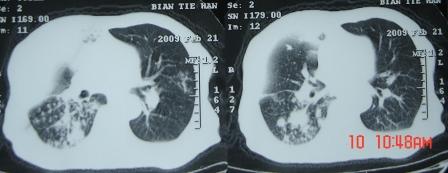

xx 男 63岁 发热 家属描述有时高热 有时低热 抗酸杆菌阴性 于2月21号 胸片及ct

3月10号复查

右肺上叶干酪性肺炎并两肺支气管播散。

考虑右肺上叶干酪性肺炎并支气管播散。